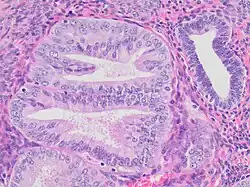

Histopathology of endometrial intraepithelial neoplasia (EIN), with its typical features:[1]

- Architectural gland crowding

- Altered cytology relative to background glands

- Minimum size of 1 mm

- Exclusion of adenocarcinoma

- Exclusion of mimics

Mitoses should also preferably be seen. Compare to normal endometrial gland at right.